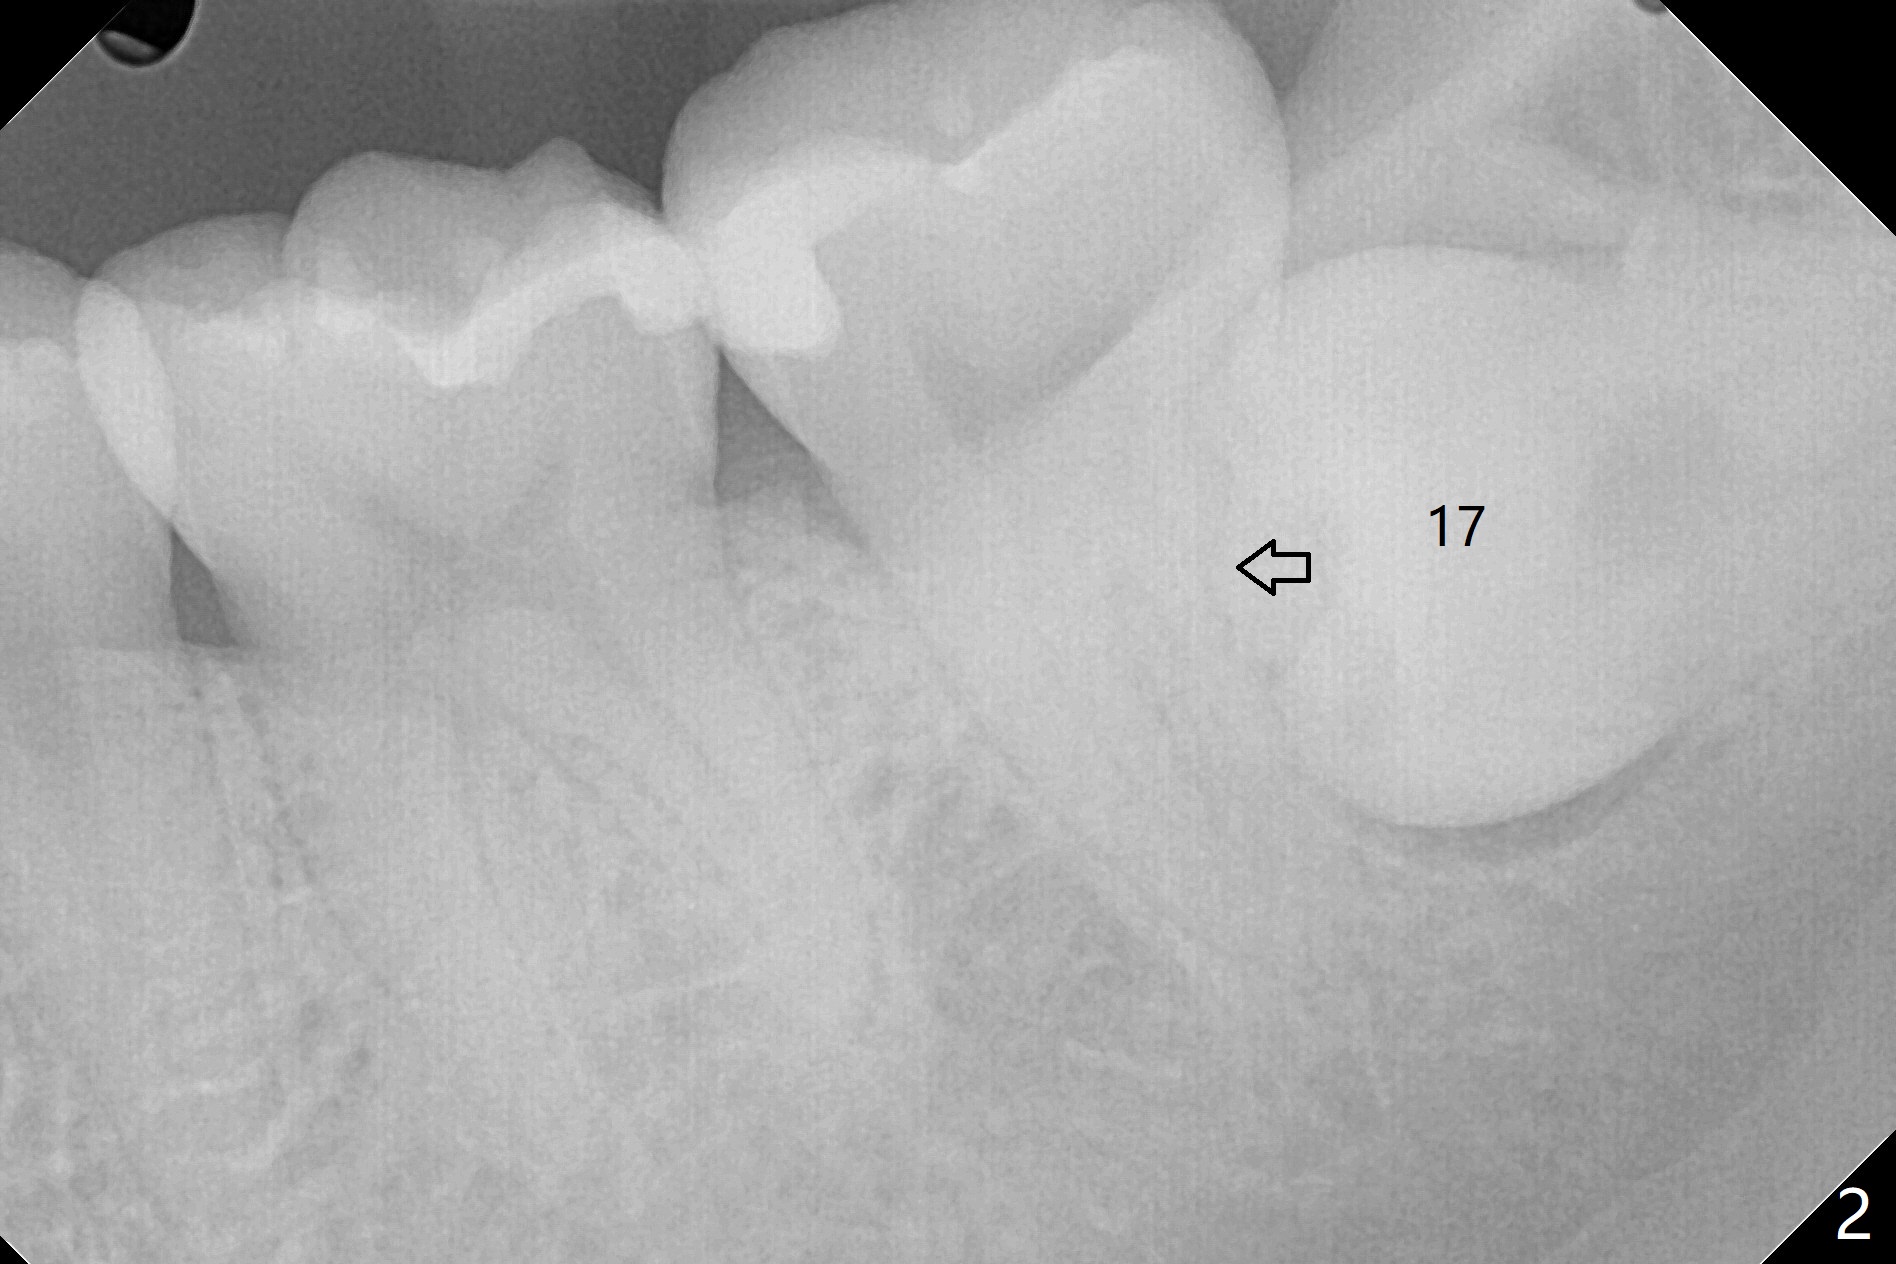

A 27-year-old woman (nervous) is going to return for #16 and 17 extraction (Fig.1). Offer sedative (Valium) if she cannot overcome fear. Take PAs for #17 and 32 to confirm Buccal Impaction, which dictates position of the accessory incision to reduce loss of bone graft in case of wound dehiscence. Place Collagen Plug (1/2 piece) in the apical portion of the sockets of the lower 3rd molars, while Augma and Osteogen Plug (1 piece) in the coronal half of #17 and 32, respectively. Place additional Collagen Plug for the remaining socket if needed before 4-0 PGA suturing as the 2nd step to decrease the chance of losing bone cement. Preop PA shows that the tooth #17 seems to be mesial (Fig.2 arrow). The accessory incision is placed mesiobuccal of the tooth #18 (Fig.4 red oblique line, Fig.6) so that it is not overlying the bony defect (Fig.4 arrowheads). Since the access to the impacted tooth is limited, small field of CT is taken (Fig.3,4), which shows the root is yet to be exposed (Fig.3 R). After tooth removal, Collagen plug is placed in the apex of the socket for hemostasis (Fig.5 C), while Bond Apatite coronal for bone regrowth (A). There is no dehiscence 11 days postop (Fig.7), although the patient complains of pain in the jaw and the temporomandibular region. The anterior portion of the external oblique ridge forms 1 year 7 months postop (Fig.8).